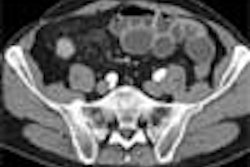

MR/CT angiography

CT angiography (CTA) is ideal for imaging accessory renal arteries. And CTA with spiral and multidetector-row scanners provides better resolution compared to MR angiography (MRA). Maximum intensity projections (MIP) and volume-rendering algorithms can also be used to analyse the dataset (Radiology, May 1999, Vol. 211:2, pp. 337-343). CTA is also very useful in providing a road map for surgery because the 3D relationship of the vessels in the renal hilum can be visualised.

However, with CTA there is risk of contract-induced nephrotoxicity in patients with baseline renal impairment or diabetes. Taking this into consideration along with the risk from radiation, MRA may be a better choice for RAS. "MRA is emerging as the most important noninvasive imaging modality for stenosis," Moorthy said.